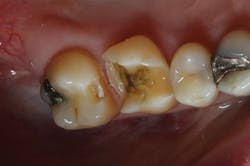

Figure 5: Bitewing x-ray shows no indication of caries on tooth No. 2Before I began prepping for the crown, I used CariVu. On the images, I saw not only a crack on the tooth that was to be crowned, but also clear caries on the adjacent tooth (figure 6). During treatment, I snapped a picture of the preparation on tooth No. 2 with an SLR extraoral camera (figure 7). I took an additional photo mid-treatment to show how far the cavity had progressed into the dentin. The bitewing didn't show any of this decay. This caries detection technology gives me a great opportunity to tell patients that I found a cavity that we would not have known about until it caused trouble. There is no surprise later and no apologies for missing an early lesion.

Figure 6: CariVu image clearly shows mesial decay on tooth No. 2While some incipient lesions can be put on a "watch list," some should be treated early. Patients don't want to wait until they are in pain or having sensitivity, and that can be avoided by detecting and restoring caries early with smaller fillings that last longer and are less damaging to tooth structure. CariVu has given me another way to prove that I have confidence in my diagnoses. When I have shown x-rays to patients in the past, some have said, "I don't see it, but I trust you." I appreciate their trust, but what I really enjoy is being able to show proof of the caries, treat it, and then follow through.